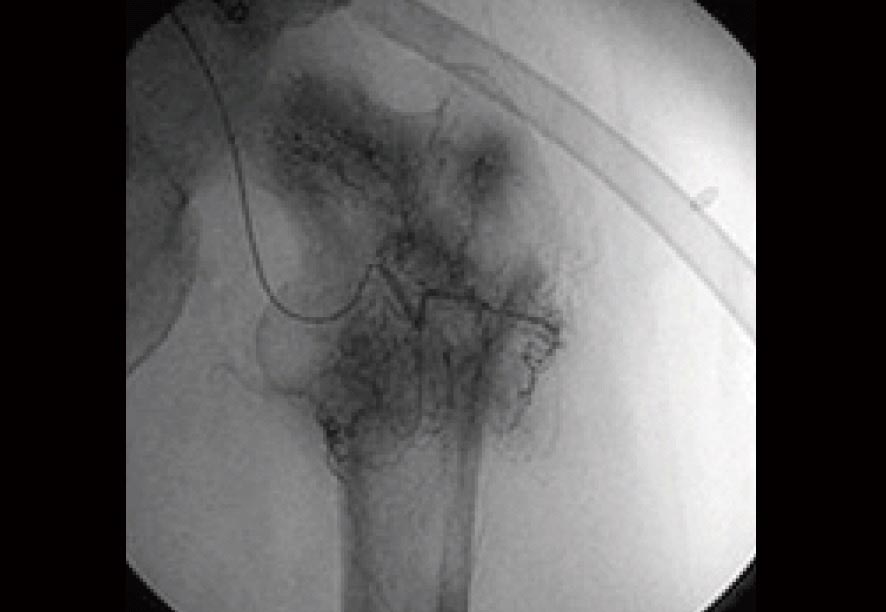

治療前のX線検査結果

参考までに、免疫治療前に実施された血管カテーテルによる骨転移の画像を見てみましょう。

この検査所見によると、左・大腿骨の周囲にはモヤモヤとしたがんの新生血管が密に認められていました(黒い部分)。

当然、この病状にいたっては歩行困難な状況であることは十分に理解できることでしょう。